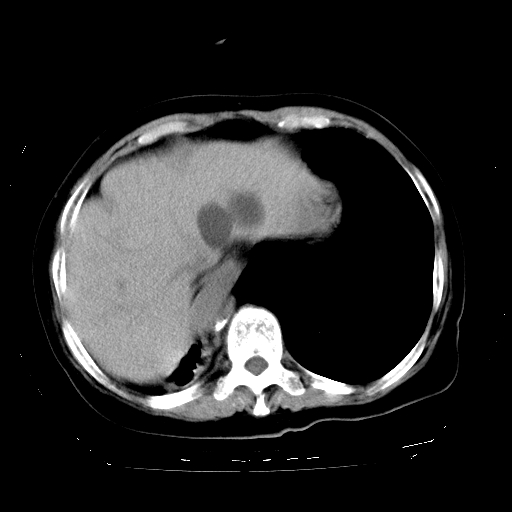

标题: CT23991:女,72岁,咳嗽、憋气一周。 [打印本页]

女,72岁,咳嗽、憋气一周,十年前曾患肺结核及胸膜结核。

1.右侧损毁肺伴胸膜钙化,2.左肺小结节灶,良性可能大,注意复查。3.肝脏左叶囊肿。4.先天性一侧肺不发育待出外(右侧胸廓无明显塌陷)。对比原片应该非常有帮助。